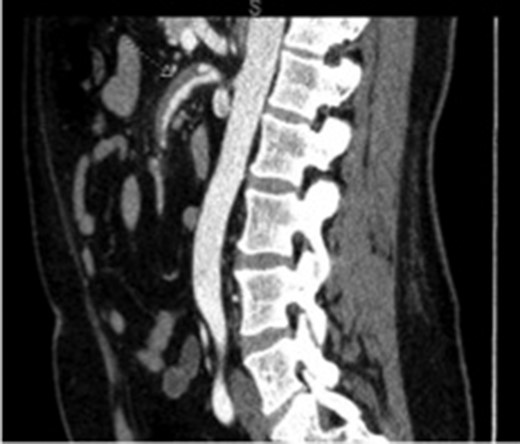

Repeat CT imaging 3 months after this hospitalization continued to show the SMA dissection with resolution of the SMA thrombus (Fig. 2). His warfarin was discontinued in exchange for a dual antiplatelet therapy.